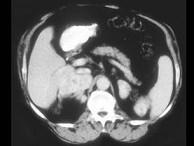

问题 女,32岁,阵发性高血压2年余,请结合所提供图像,作出诊断 ( )

选项 A、左肾上腺嗜铬细胞瘤 B、左肾上腺淋巴瘤 C、左肾上腺腺癌 D、左肾上腺转移瘤 E、左肾上腺腺瘤

答案 A